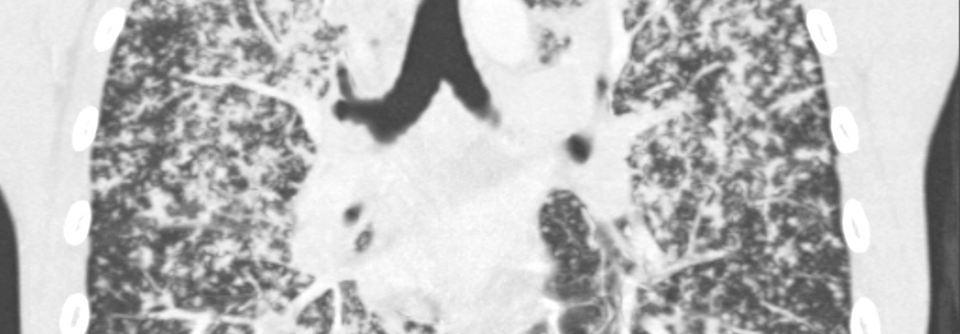

Die Lungenerkrankung steht meist im Vordergrund und ist Hauptgrund für die Mortalität. Der visköse Schleim auf den Epithelzellen der Bronchialschleimhaut beeinträchtigt die mukoziliäre Clearance und verengt die Atemwege. Die Kolonisierung der Atemwege durch pathogene Keime wird dadurch begünstigt. Besonders gefürchtet ist die Besiedlung mit Pseudomonas aeruginosa. Diese Keime können in eine mukoide Form mutieren und bilden Biofilme, wodurch sie vor dem körpereigenen Abwehrsystem und Antibiotika geschützt sind. Durch die chronische Inflammation und rezidivierende Bronchitiden und Pneumonien wird das Lungenparenchym im Verlauf irreversibel geschädigt, was letztendlich die Lebenserwartung begrenzt.

•  Im Verlauf Bronchiektasen und obstruktives Emphysem

•  Fibrose mit pulmonaler Hypertonie und respiratorischer Insuffizienz im Spätstadium

• Bildgebung des Thorax